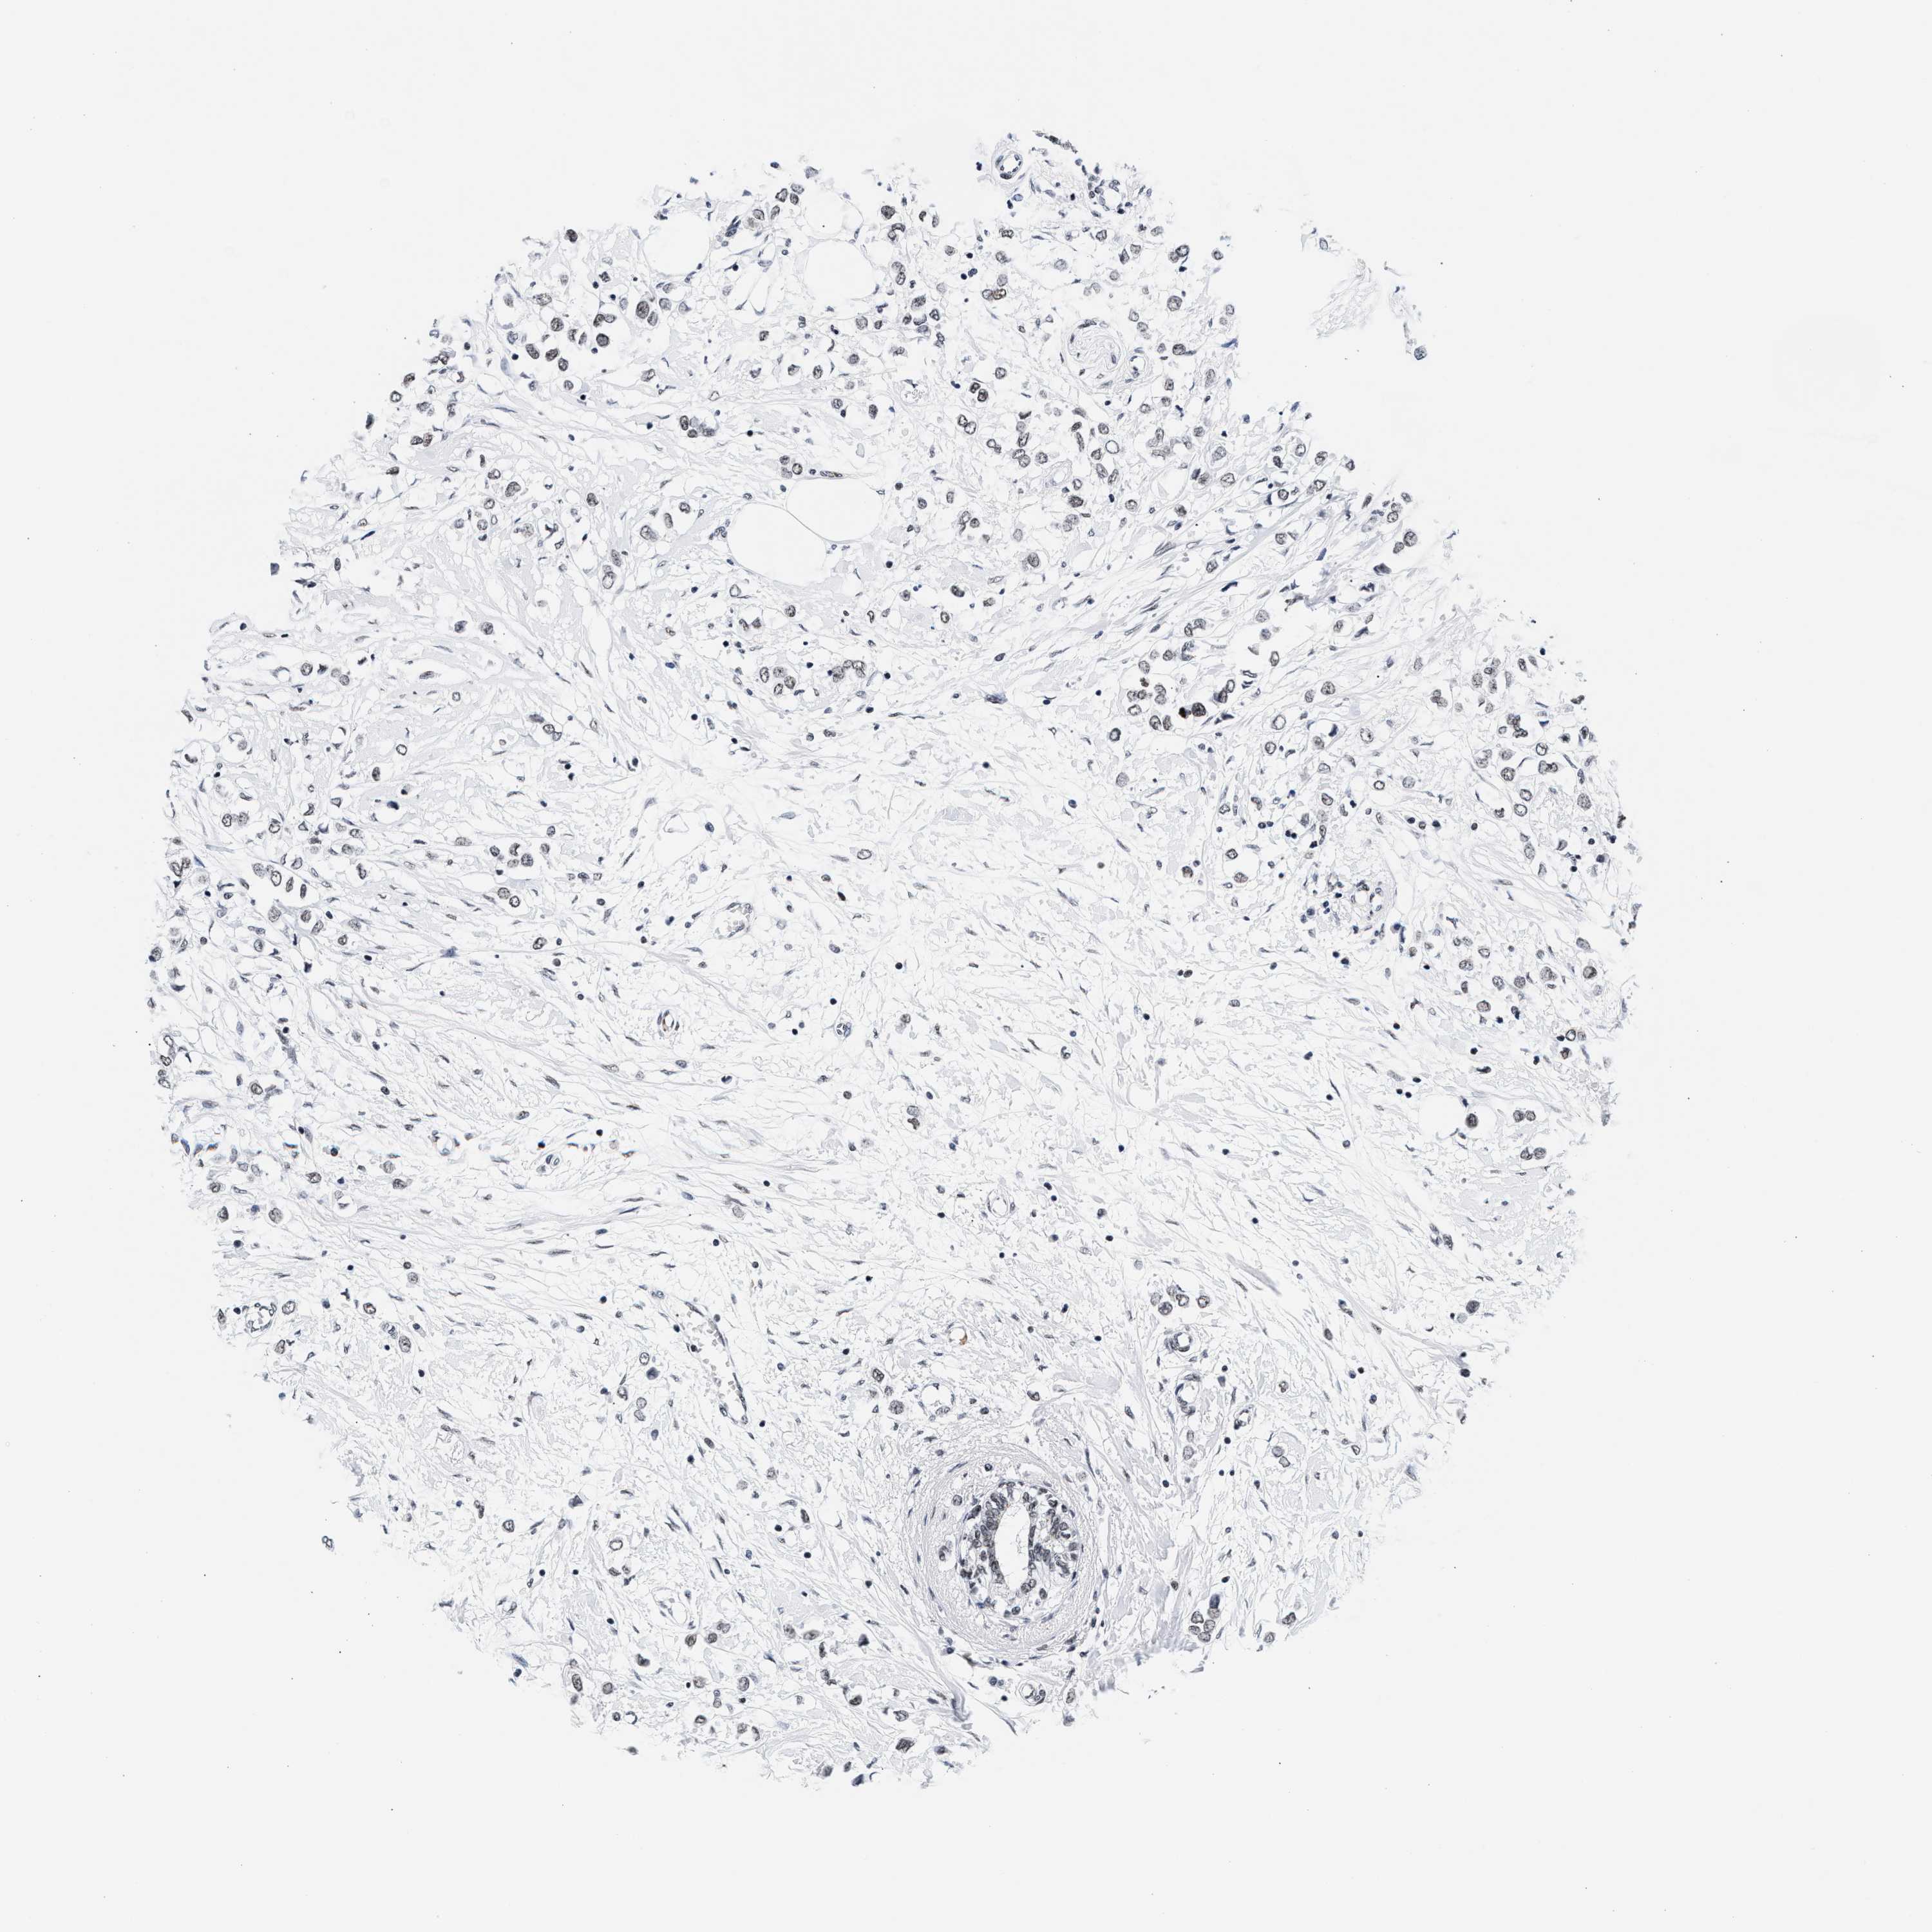

RAD21

CANCER BREAST CANCER Show tissue menu

BRCA TCGA BRCA VALIDATION PROTEIN EXPRESSION

ANTIBODIES

AND

VALIDATION